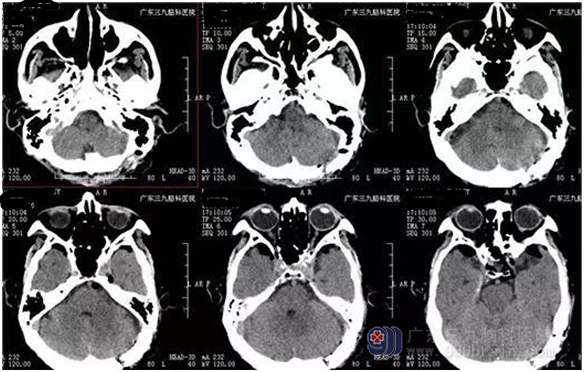

神经外一科接诊了一位86岁的高龄患者,8年前开始出现左侧面部疼痛,在当2家医院医治,但无明显改善。老人描述自从得了这个病,洗脸、刷牙甚至说话、吃饭都不敢太用力,太难受了!为求进一步治疗,来我院就诊。入院后完善检查,诊断:三叉神经痛。神经外一科主任张良主刀为老人行左侧三叉神经痛微血管减压术, 术程顺利,经系统治疗后患者恢复良好,未有颜面部疼痛症状。

广东三九脑科医院神经外一科张良主任介绍,三叉神经痛微血管减压术的原理是找到三叉神经和责任血管,用Teflon垫片将血管与神经根隔离。一旦责任血管被隔离,产生刺激的根源就消失了。

接近3/4的患者在接受微血管减压术治疗5年后仍然无痛且停药,这些患者在随访到20年后仍有2/3疼痛消失,不用药物。因此,三叉神经痛微血管减压术是行之有效治疗手段。